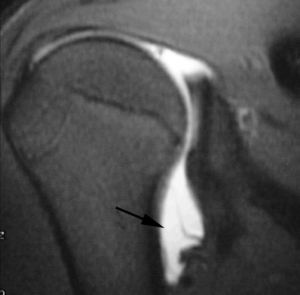

POLPSA (posterior labral periosteal sleeve avulsion)

Esta lesión se asemeja a la ALPSA, pero ocurre en el borde glenoideo posterior. El LG se halla desplazado hacia dentro y por detrás del borde glenoideo posterior. El mecanismo de producción del POLPSA es una dislocación posterior, y por tanto se puede encontrar también un Hill Sachs invertido19 (fig. 14).

. Artrorresonancia axial T1 con supresión grasa donde se observa una rotura del labio glenoideo posterior con desplazamiento posteromedial (flecha). Nótese la situación del labio glenoideo en comparación con una rotura sencilla, no desplazada, que se observa en la figura 13. Obsérvese la presencia de una lesión de Hill-Sachs invertida (cabezas de flecha), en relación con una dislocación posterior con reducción.Lesión de Bennett